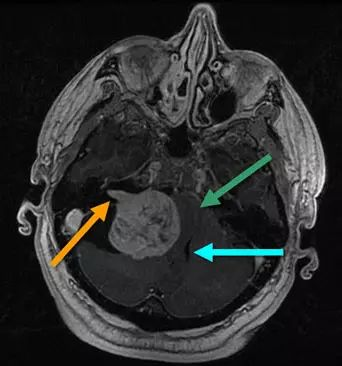

桥小脑角区脑膜瘤占全部脑膜瘤的5%~10%。这些病变需与前庭神经鞘瘤和转移瘤区别开来;影像学特点有助于鉴别诊断。下图为增强MRI扫描T1加权像,显示了经典的前庭神经鞘瘤,表现为“冰淇淋”征,呈圆柱形状,延伸至内耳道(橙色箭头)。神经鞘瘤缺乏脑膜瘤附近常见的硬脑膜增厚。脑干(绿色箭头)被肿瘤所扭曲,导致四脑室(蓝色箭头)受压,造成患者脑积水。此人表现为严重的共济失调与脑干和小脑功能障碍。

下图为MRI增强扫描,显示了位于内听道略后方的硬脑膜基底肿瘤。该肿瘤较大特点为不延伸至耳道,这提示它不是一种前庭神经鞘瘤;较可能的诊断是脑膜瘤。与之前的影像学相比,该病例局部占位较小,虽然这不是脑膜瘤和前庭神经鞘瘤之间的鉴别特征。